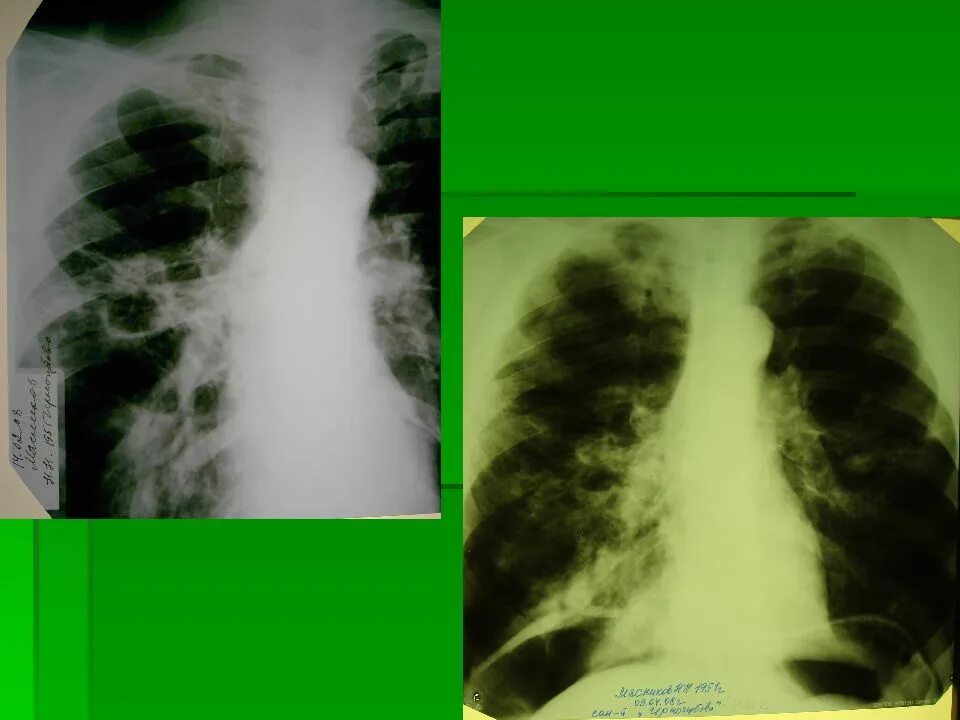

Коллапсотерапия при туберкулезе